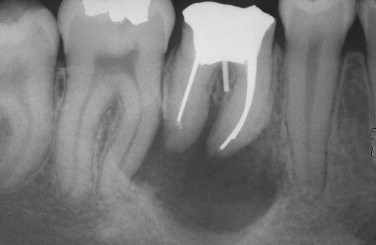

What is this 3rd most common type of globulomaxillary radiolucency?

Lateral periodontal cyst

Is this a lateral periodontal cyst or radicular cyst?